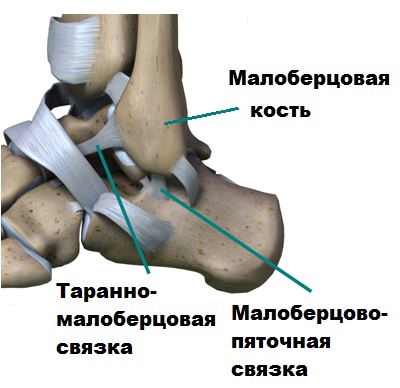

Анатомические фото голеностопного сустава и его суставных поверхностей